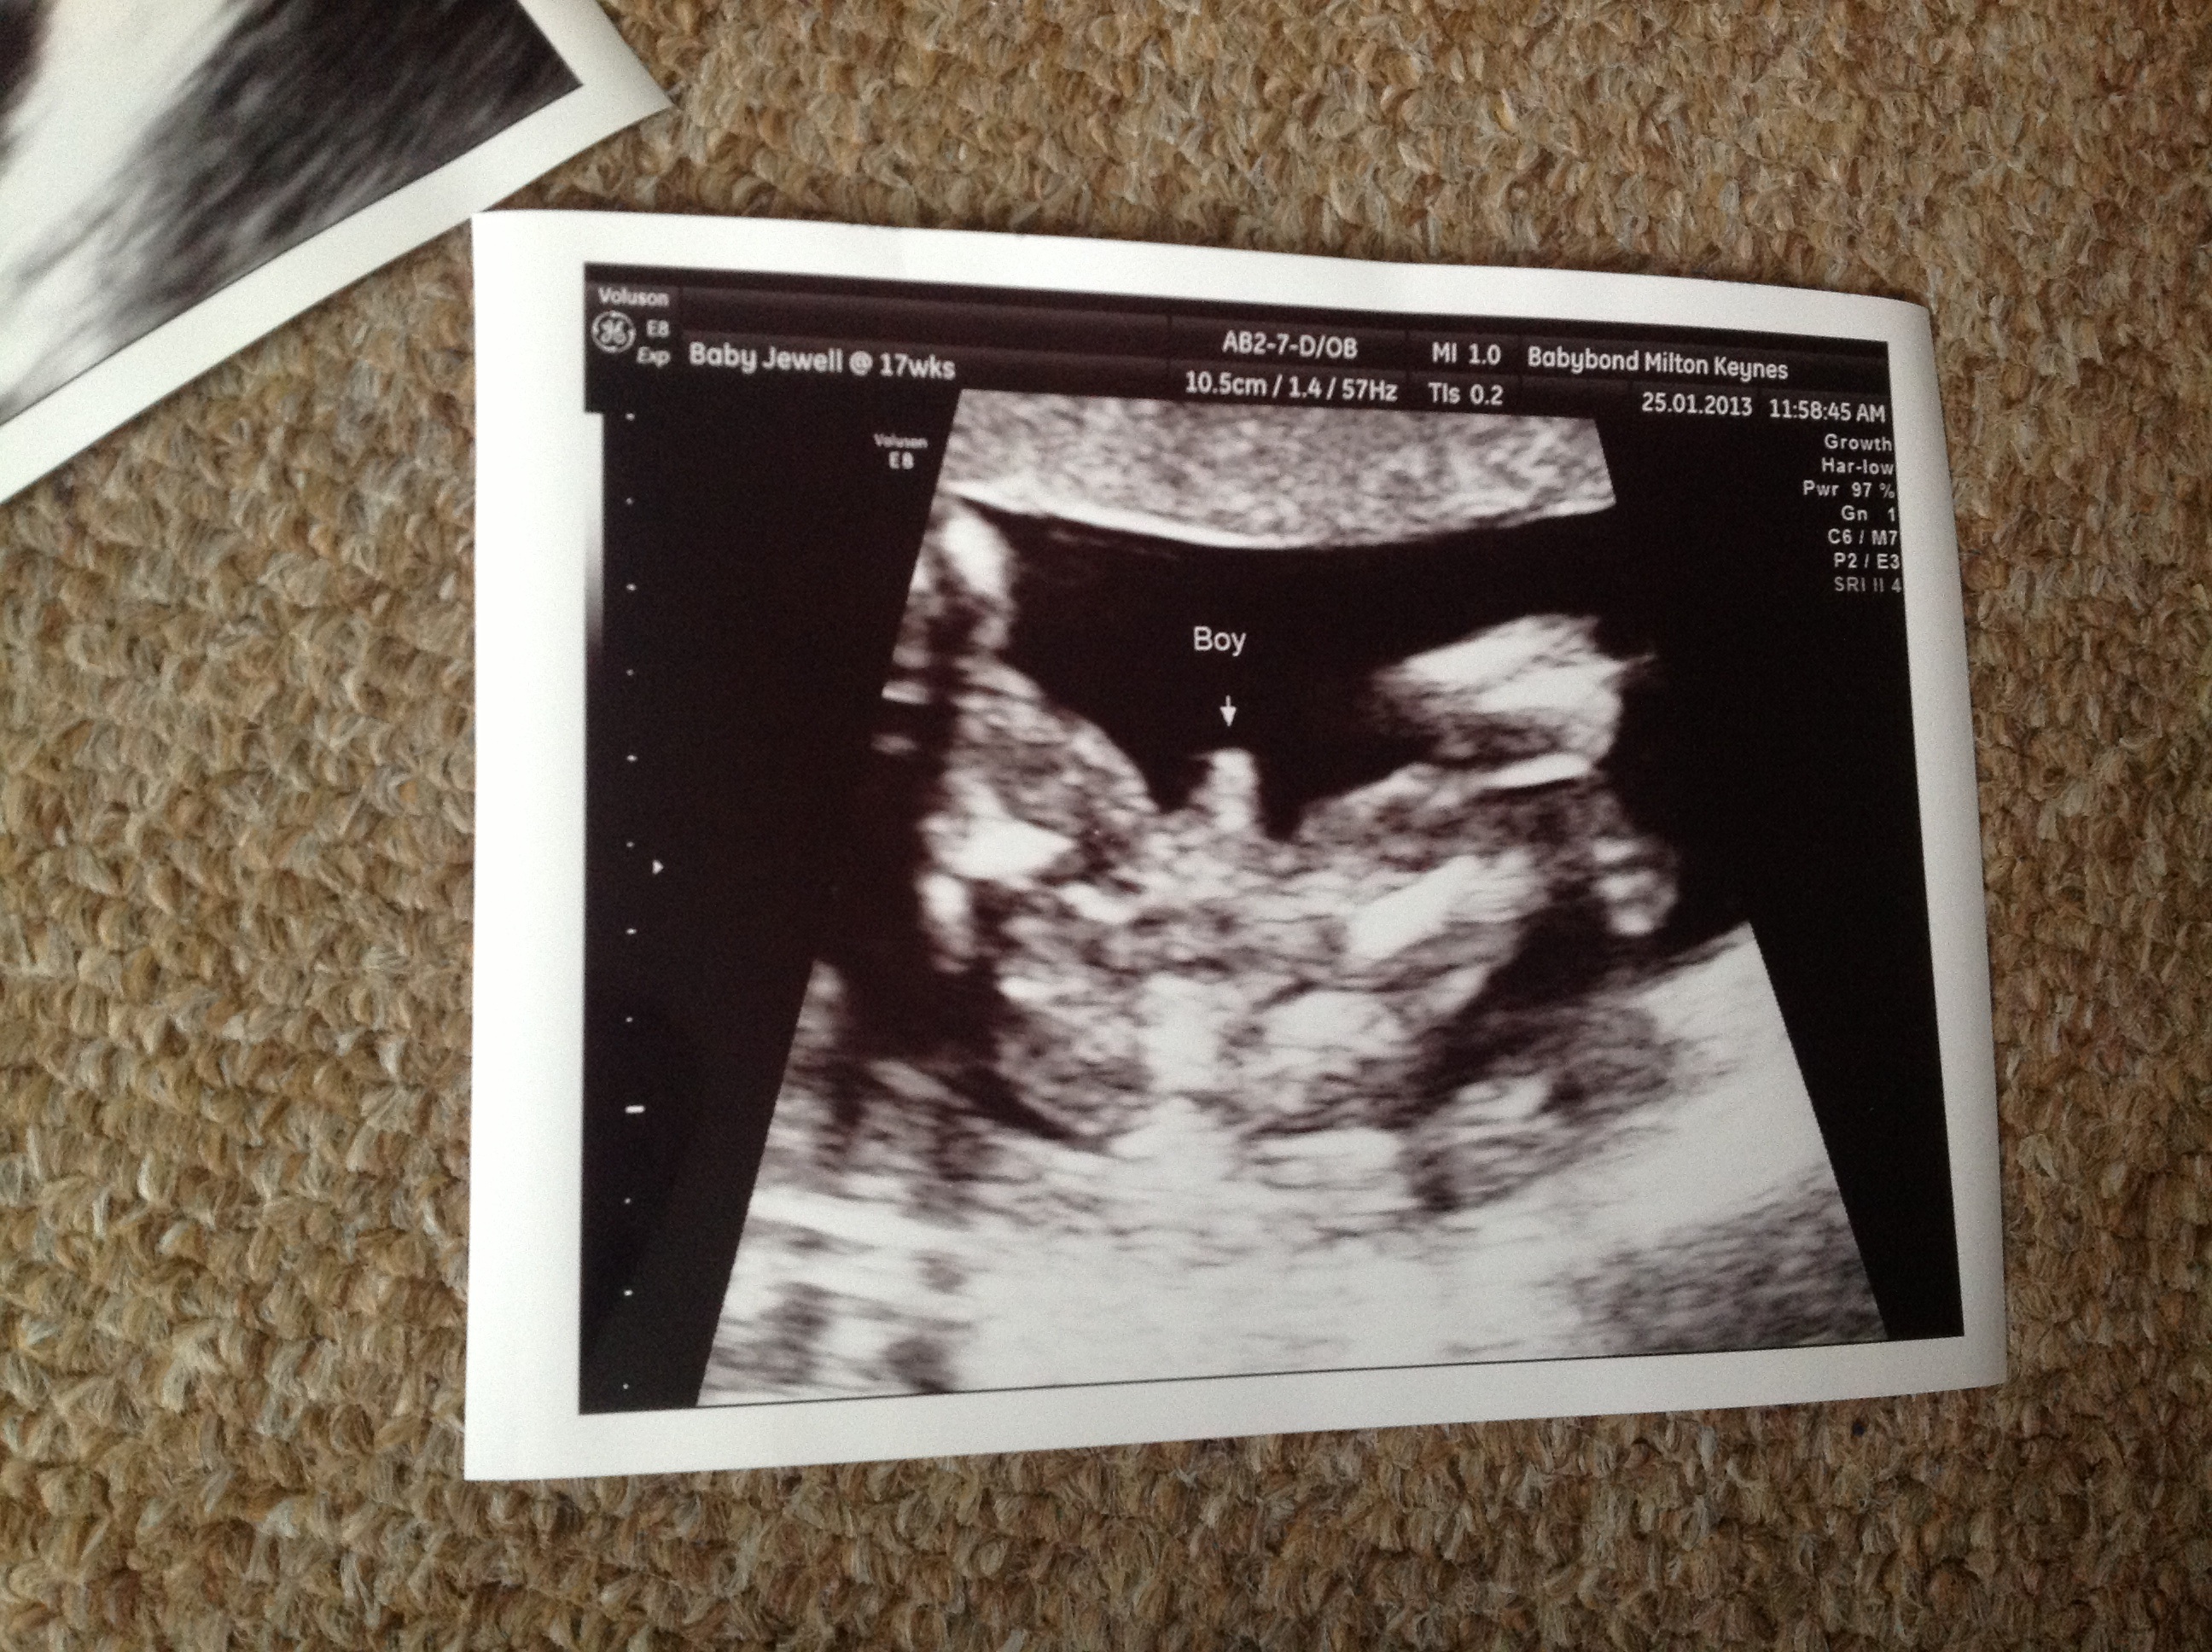

im 17+4 potty shot defo boy !!!!Attachment 8375

Oh YAH! He sure is showing off...congrats on your SON!

Congrats on your baby boy!! He sure does look proud :). I know bananas sway boy, but I'm pretty sure the 10 days bedding straight would sway girl just for others wanting to sway. You sure did get a boy though!! Big congrats!!:DS: